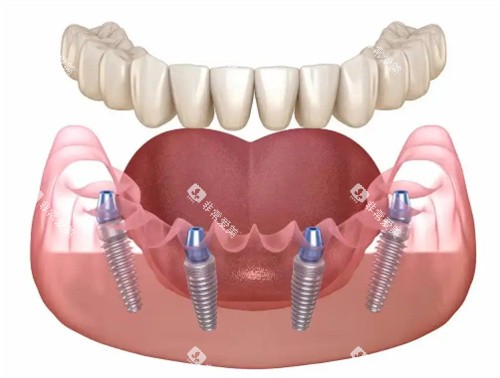

诊所擅长骨性龅牙矫正与ALL-on-4半口全口种植技术,田场磊医生团队通过微笑美学设计,使种植牙与天然牙形态协调度提升。